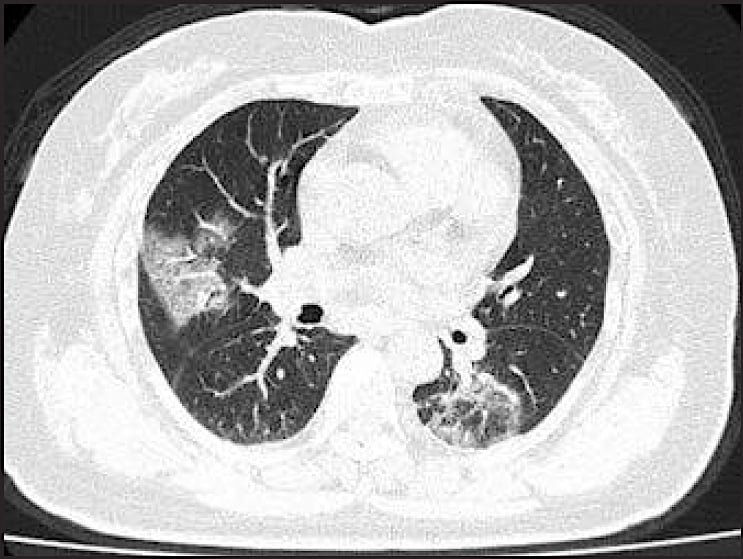

A chest CT scan of a 79-year-old woman who presented with fever, dry cough, and chest pain for three days. Her husband and daughter-in-law had been recently diagnosed with coronavirus disease. The patient expired 11 days after admission.(Courtesy of Song F, Shanghai Public Health Clinical Center, Shanghai, China)